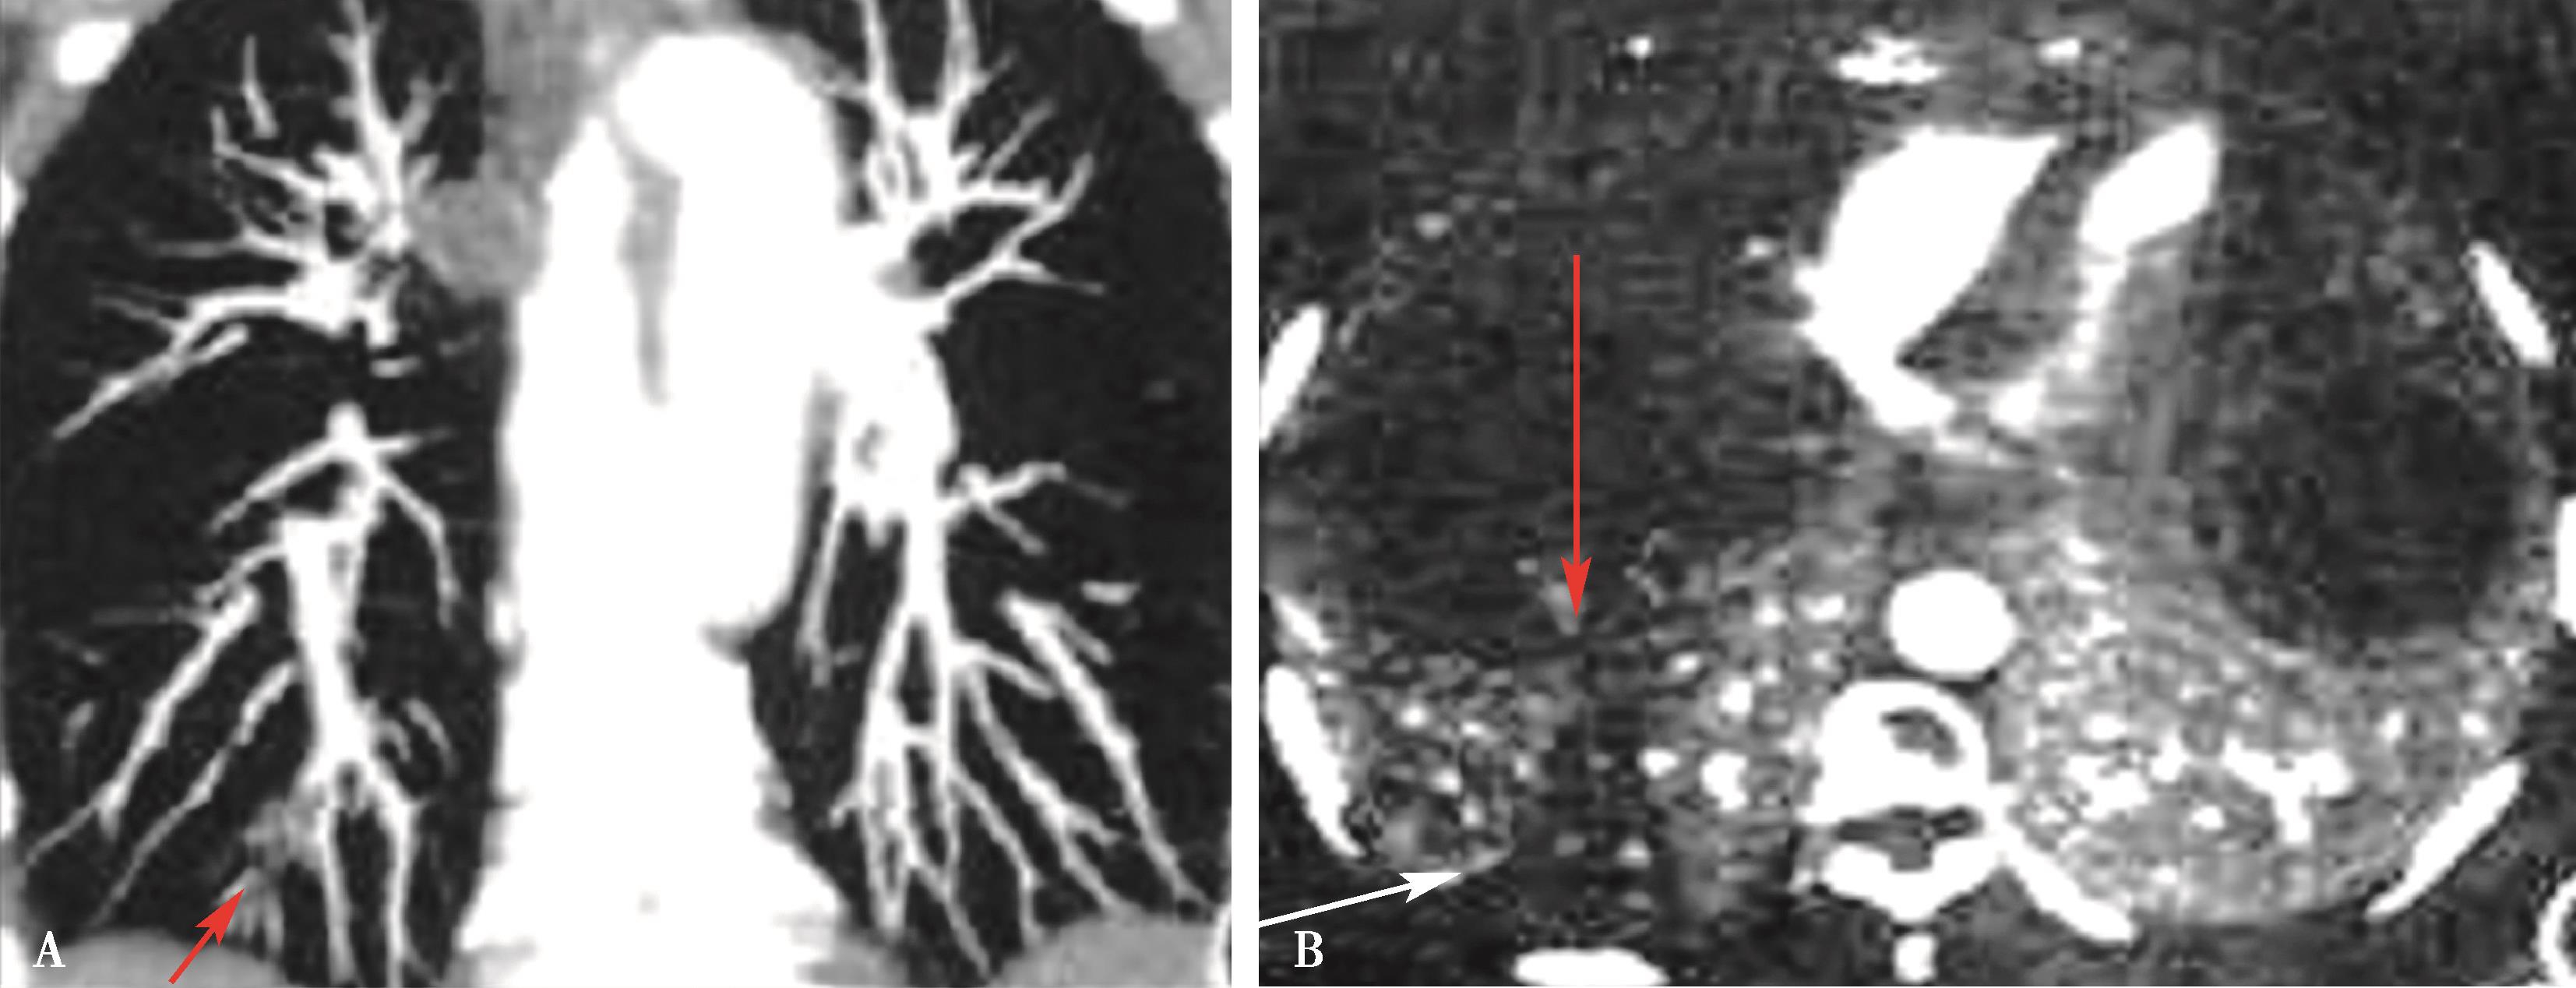

图8-1-5 CTPA两期扫描应用:患者,男,37岁,二尖瓣狭窄,肺循环高压,怀疑肺栓塞。第一期右肺下叶基底段对比剂充盈不充分(ABC↑);第二期充盈充分(DEF↑),排除肺栓塞诊断

(二)双期扫描法(图8-1-5)

1.患者仰卧位,足先进,仰卧于检查床上。对检查范围以外的部位用铅衣、铅帽遮盖做好防护。

2.对比剂 对比剂浓度370mgI/ml,采用单筒高压注射器团注,流率为4.0~5.0ml/s,对比剂总量为70~90ml,如加做下肢静脉造影,可增加对比剂剂量为120~150ml。

3.扫描的范围 从肺尖到膈肌。

4.扫描采用的对比剂跟踪技术,监测层面设定在上腔静脉入右心房的层面,ROI定为上腔静脉,触发阈值定义为80~100HU。

5.当ROI的CT值达到阈值时启动增强扫描程序。实行双期扫描,第一期为肺动脉期,从肺尖扫描至膈肌,第二期为主动脉期,由膈肌扫描至肺尖,双期扫描范围一致。双期扫描的意义在于:①充分保证了对比剂团注时间与肺动脉CT数据采集时间的吻合;②肺动脉高压或/和右心功能不全循环时延长者,是一弥补措施;③多期观察可以辨别对比剂充盈不均造成的假象;④有利于对肺灌注的评价;⑤主动脉期可以兼顾观察左心系统的病变。